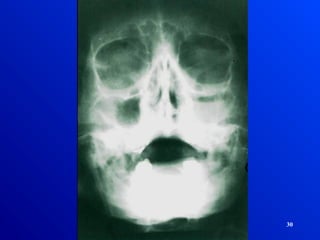

28 RINOSINUSITIS 1. Interrogatorio 2. Sintomatología 3.Examen Físico 4. Exámenes complementarios DIAGNOSTICO

• 29.

• 30.